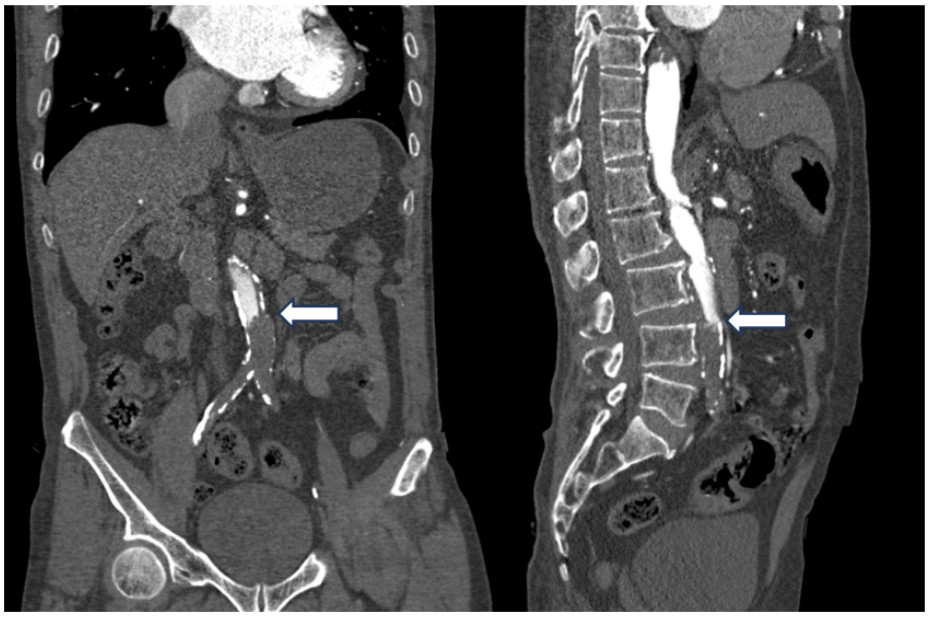

既往史:有高血压病史10年余,规律降压治疗,未监测血压。房颤病史2年余,2022年11月在本院超声心动图显示左心房见一不均质低回声团,位置随心动周期漂动(17 mm×16 mm)”(见图 1),左房前后径40 mm,左右径46 mm,上下径70 mm。LVEDD 39 mm,LVEF:60%。二尖瓣E峰0.92 m/s,最大压差3.39 mmHg(1 mmHg=0.133 kPa)。反流面积3.8 cm2,二尖瓣口频谱呈单峰。舒张期二尖瓣口前向血流,E < A,无舒张功能不全。进一步行经心脏超声造影提示:Flash后,左心室心腔内团块未见明显灌注(见图 2)。

| 注:左房内可见团块样回声影(箭头处),约17 mm × 16 mm 图 1 患者经胸腔超声心动图 |